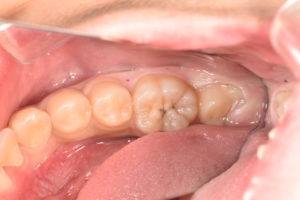

左下第一大臼歯にう窩がみられたため、レントゲン写真で虫歯の範囲を確認すると歯髄に近接した透過像をみとめた。症状はまったくなく、若年者でもあったため歯髄の保存を試みた。虫歯の除去中に容易に露髄し、歯冠部歯髄は一部壊死していたため歯頚部にて断髄を行い、MTAセメントにて歯髄保存を試みた。一定期間経過観察の後、症状の無いことを確認した後、ダイレクトボンディングにて歯冠修復を行った。

さらにダイレクトボンディングという方法で虫歯でなくなった部位を修復することで、歯質を可能な限り温存することができ、見た目も自然なものとなります。